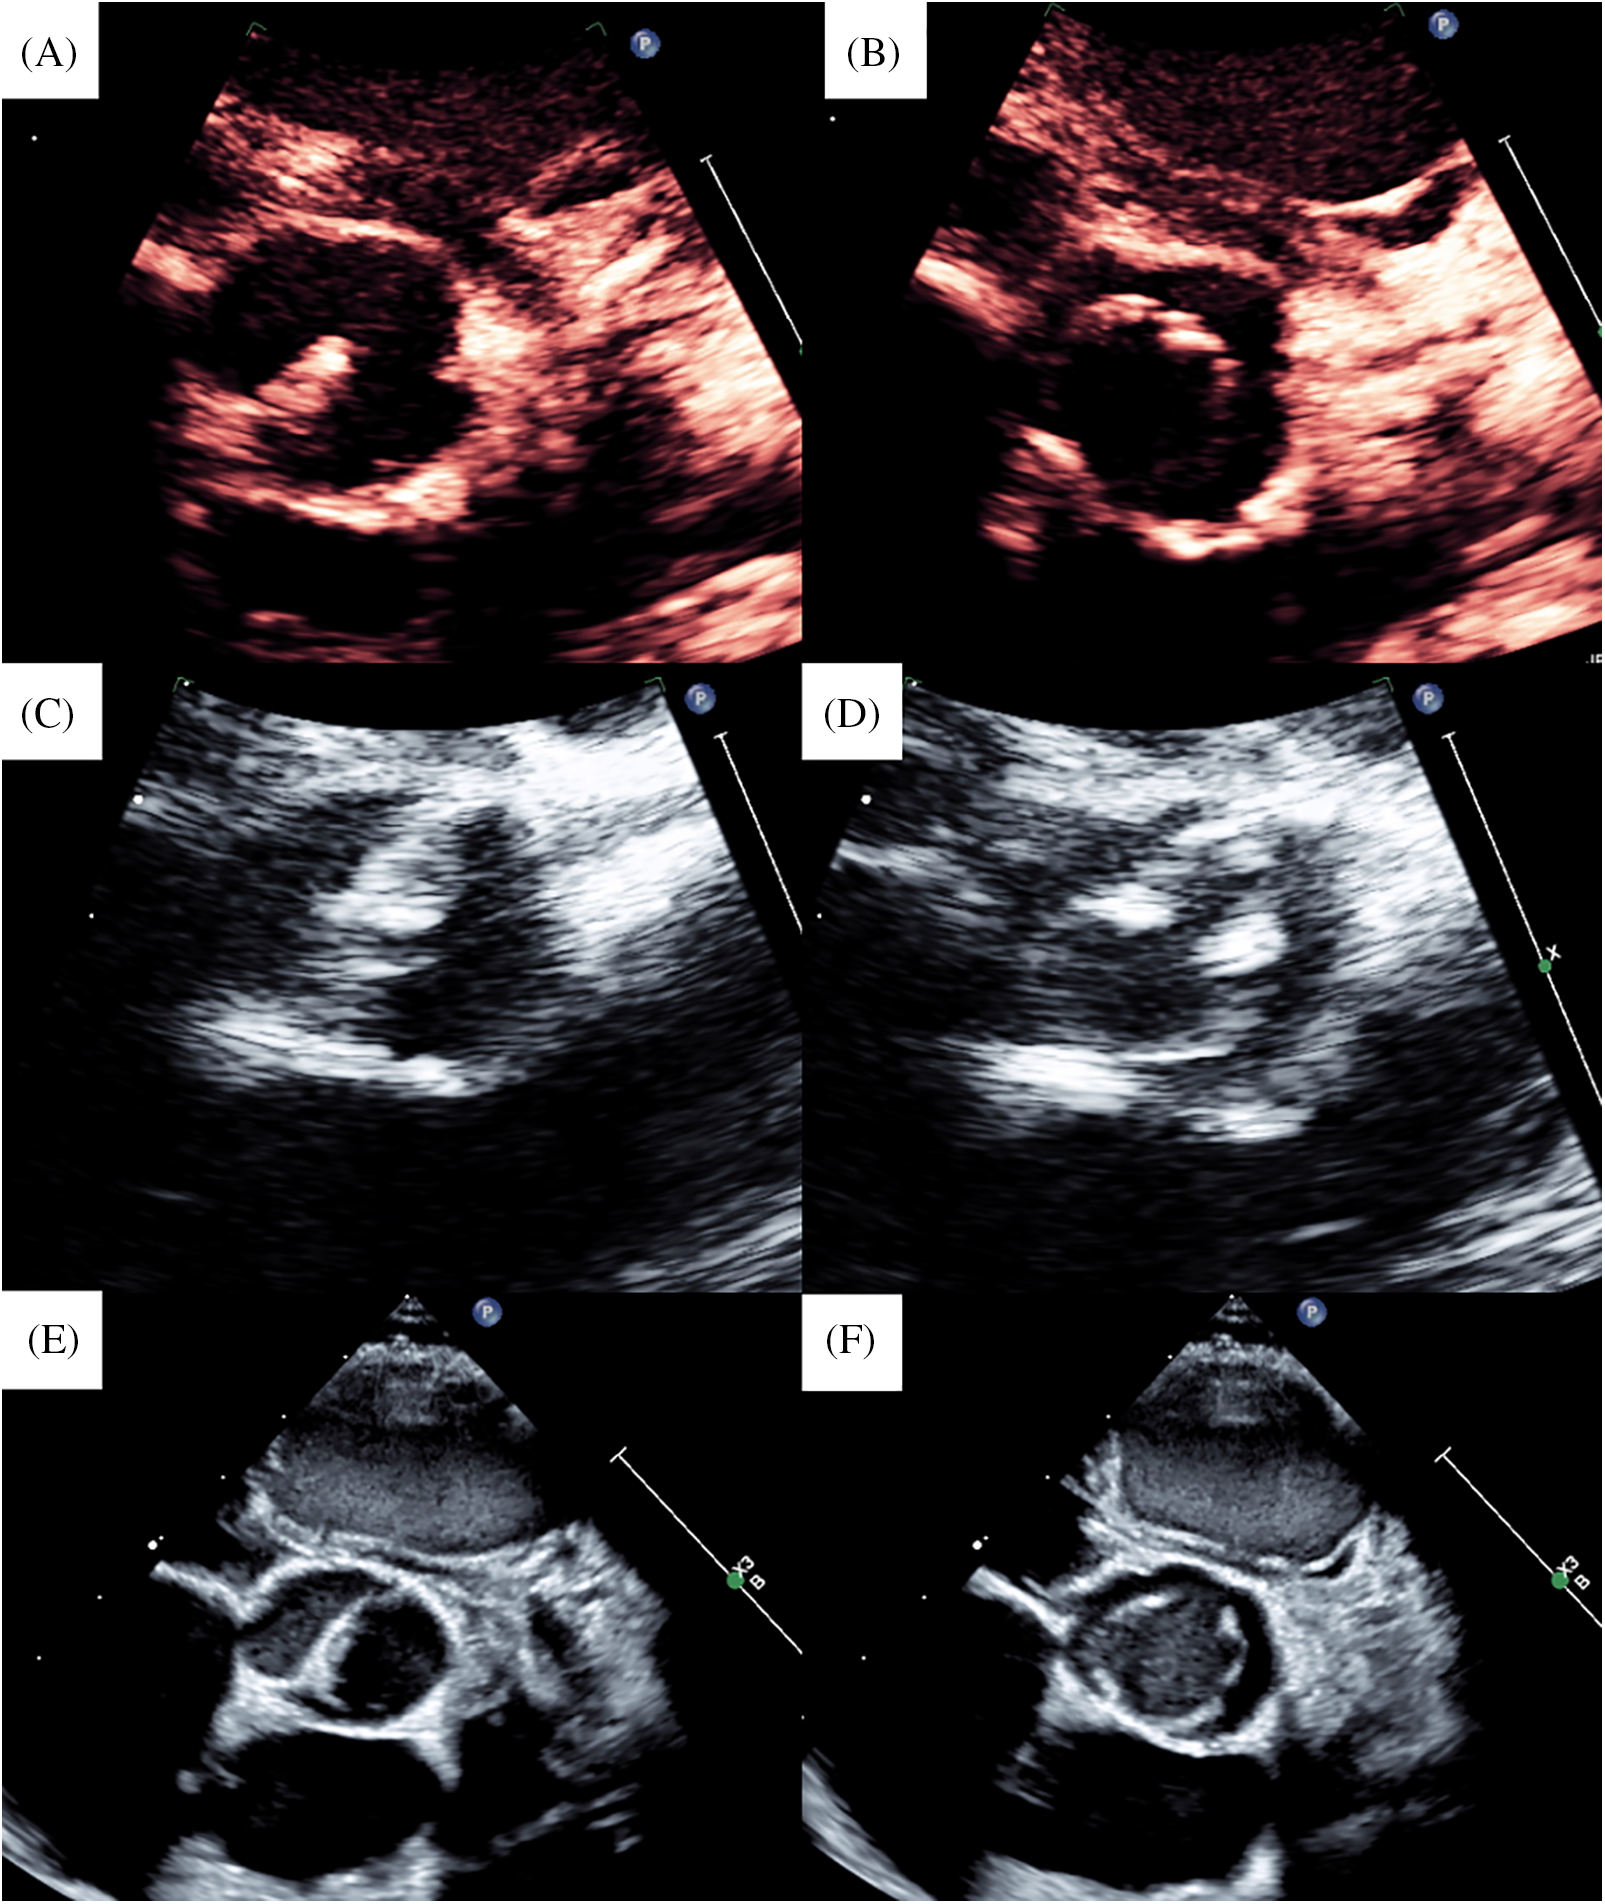

A 2-month-old male neonate diagnosed with cAS, coarctation of the aorta, atrial septal defect, left pulmonary artery stenosis, and persistent left superior vena cava during the fetal period was delivered via cesarean section at 38 weeks and 5 days and weighed 3.15 kg. Moreover, he was diagnosed with bronchial stenosis, which was repaired at the age of 1 month. He weighed 3.7 kg at the age of 2 months, but his cAS worsened. Transthoracic echocardiography revealed that his aortic annular diameter was 8.7 mm (111% of the normal, Z score = 2.0) with a unicuspid aortic valve (Figs. 6A and 6B). We performed aortic valve repair by bicuspidization with glutaraldehyde-treated (3 min) autologous pericardium using the open-sleeve technique. His operative details have been previously reported [1]. Concomitantly, we performed coarctation repair, atrial septal defect closure, left pulmonary artery plasty, and translocation of the left superior vena cava to the right superior vena cava. The cardiopulmonary bypass and cardiac arrest times were 244 and 122 min, respectively. Postoperatively, AR was trivial, and the peak velocity through the aortic valve was 1.5 m/s (Figs. 6C and 6D). The peak velocity at the anastomotic site of the aorta was 1.5 m/s. A follow-up at 6 years postoperatively (Figs. 6E and 6F) revealed mild AR and a peak velocity through the aortic valve of 1.1 m/s. The peak velocity at the anastomotic site of the aorta could not be measured, but blood flow at the descending aorta did not show a coarctation pattern. His aortic annular diameter increased along the normal annular diameter (Fig. 5), with a recent aortic annular diameter of 17.1 mm (126% of normal, Z score = 3.6).

Figure 6: Echocardiogram of case 2. (A) Preoperative image in diastolic phase. (B) Preoperative image in systolic phase. (C) Postoperative image in diastolic phase. (D) Postoperative image in systolic phase. (E) Last follow-up image in diastolic phase. (F) Last follow-up image in systolic phase